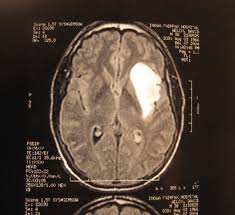

Radiosurgery is a non-invasive cancer treatment in which targeted radiation beams are used to destroy or shrink tumours. But the Novalis Tx device tailors these beams to match the exact shape, size and position of a tumour in the body. This means that a more intense beam can be used without causing damage to surrounding tissue. The device can also manoeuvre the beams to reach tumours deep inside the body, such as in the spinal cord, which were previously inaccessible.

The system uses X-ray images of a tumour to monitor its position, and can even adapt when growths - such as those in the lungs - move as the patient breathes. It responds by only zapping the tumour when it returns to its original position after each breath (see video, above).

Patients who would normally have to spend months recovering from complicated open surgery to remove brain tumours can now be treated in one session and return to normal life the following day. In some cases, cancer patients can be treated in just fifteen minutes.